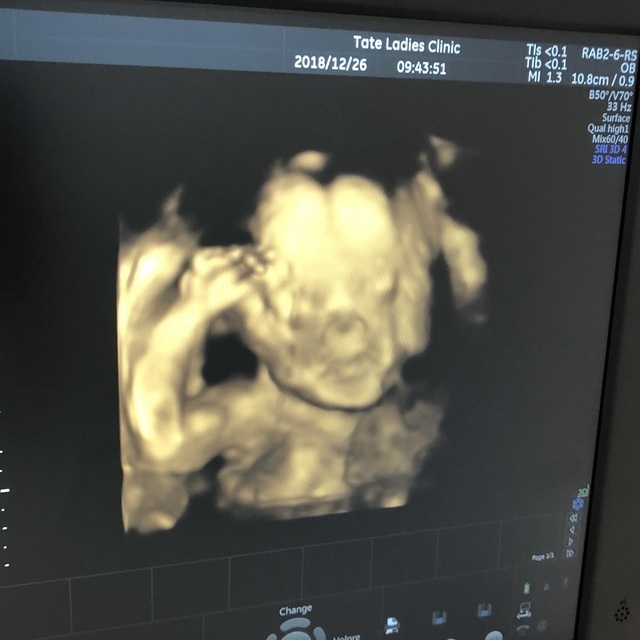

24週4日(24w4d・女の子)|むむーむ さん(24歳)

エコー写真撮影時のエピソード:

3D、4Dが見たくてわざわざ別のクリニックを予約。夫、両親、4人でらいいんしました。

今まで2Dばかりでなんとなくしかわからなかったお顔、性別がしっかりとわかり、手を開いたり、伸びをしたり、目をこする様子がハッキリと見え、今にも抱きつきたい想いになった事を覚えています。

妊娠7ヶ月、まだまだ小さいのにもうこんなにもハッキリ人間なのを(当たり前ですが改めて。笑)実感し、小さな命に感動し、その場で4人とも涙ぐんだいい思い出です。